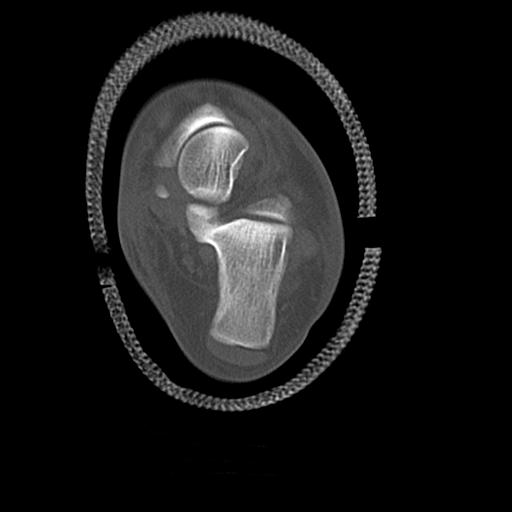

49554 3/13 膝 4R 3/16 4R 1/18 2R 78歳男性 膝蓋骨骨折